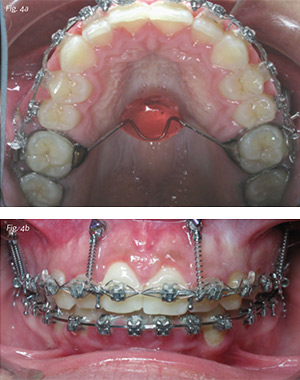

Damon standard torque .022 appliances were placed in both arches. Routine leveling and alignment was achieved with a standard archwire sequence to 19x25 stainless steel archwires, requiring six months of treatment time. A soldered transpalatal arch was placed with 6mm of clearance relative to the palatal tissue and an acrylic button to provide comfort for the tongue and encourage additional intrusive forces by the tongue upon the maxillary dentition (Fig. 4a). Vector TADs (6mm) were placed at the mucogingival junction in the buccal vestibule between the upper central and lateral incisor roots and 8mm vector TADs between the roots of the upper second bicuspids and molars. Intrusive forces were applied to the posterior segments with 250gm NiTi coil springs between the upper first molars and second bicuspids. Smaller intrusive forces of 150gms each were applied to the archwire between the maxillary central and lateral incisors so as to maximize molar intrusion and autoration of the mandible while simultaneously reducing gingival display (Fig. 4b). The intrusive forces were applied for a total of 14 months. During the course of treatment, the upper right posterior mini screw failed twice, as well as the upper right anterior mini screw once, due to root collisions during intrusion. In both instances of failure, the failed mini screw was removed and the site allowed to heal for two weeks prior to reinsertion at a site just apical to the original site. The TPA was then removed and final detailing of the posterior occlusion, anterior root torque, ideal overbite and overtjet relationships were achieved with 19x25 TMA and light interarch elastics for an overall treatment time of 24 months. Some gingival contouring was performed with a diode laser to maximize enamel display and establish pleasing gingival margin symmetry. Osseous crown lengthening was not necessary as reported by others.1 Bonded wire retainers were placed and night time Essix retainers were delivered.